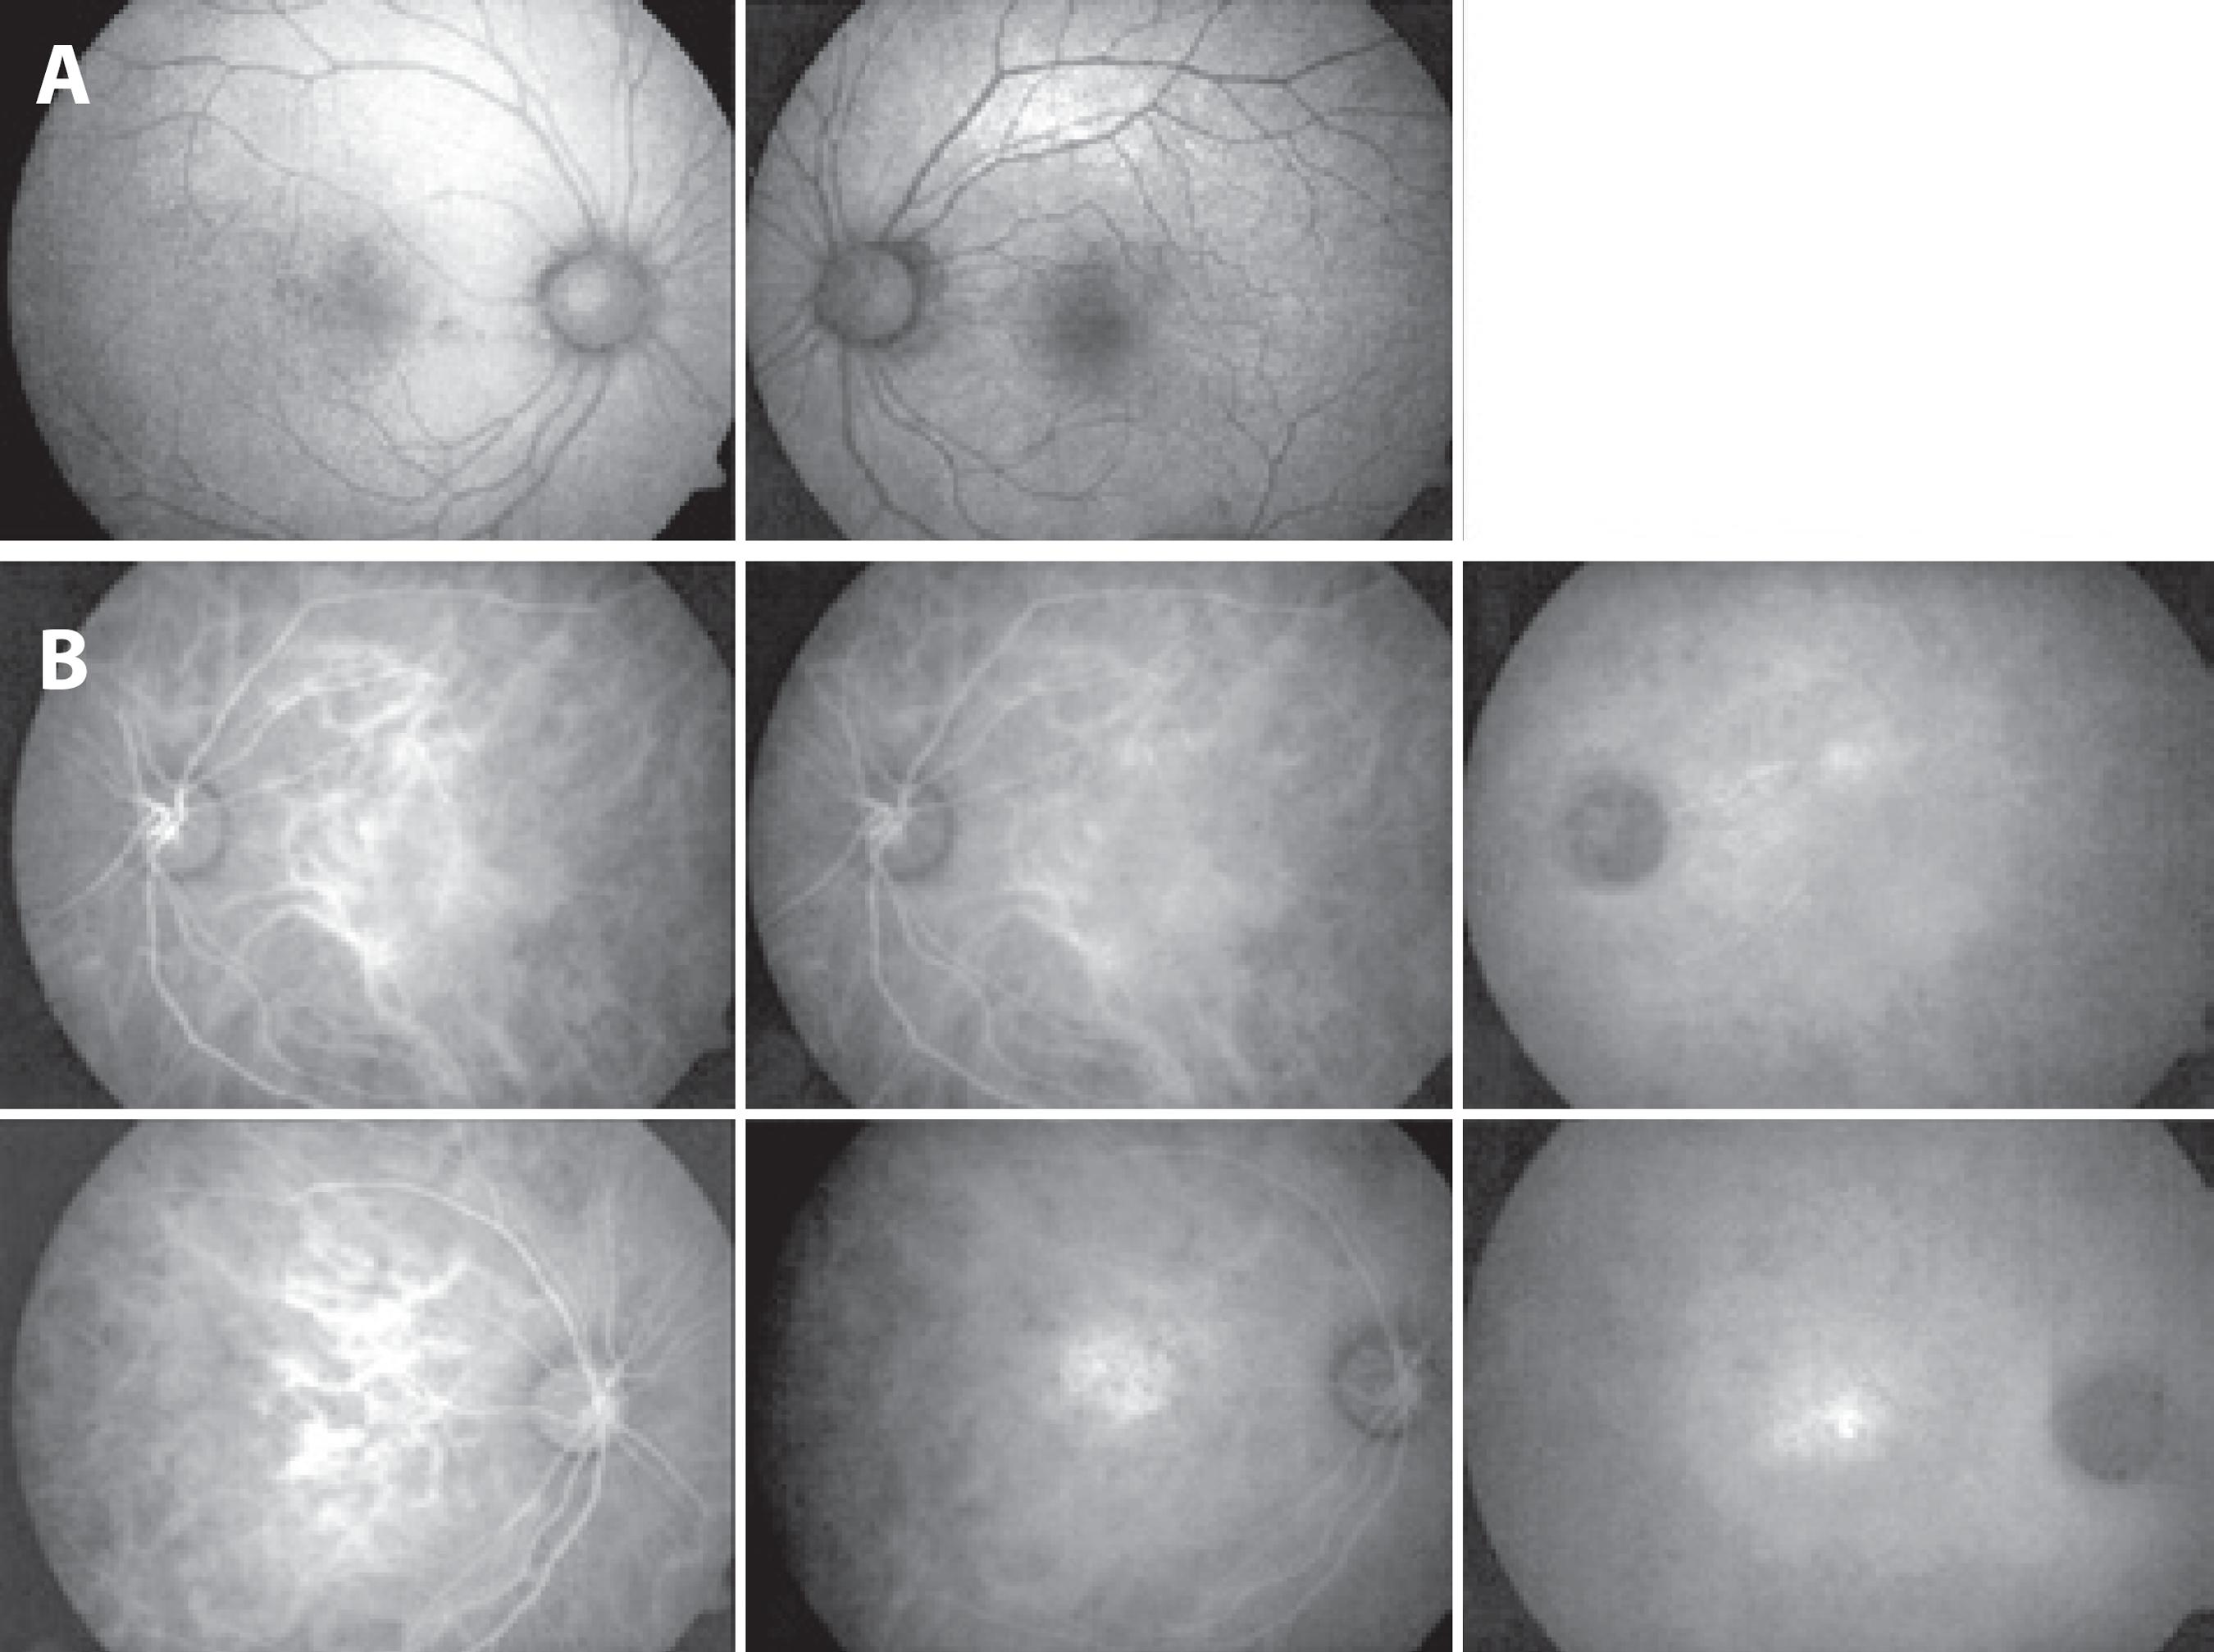

We report the case of a 58-year-old white male who presented three years previously with impaired visual acuity affecting the left eye. The visual acuity was 20/25 in the right eye and 20/200 in the left eye. Ocular fundus examination revealed reduced fundus tessellation in the right eye (Figure 1 A). A semitranslucent epiretinal membrane caused macular distortion. Membrane contraction displaced the paramacular vessels toward the horizontal raphe in the left eye (Figure 1 A). Fluorescein angiography (FA) of the right eye demonstrated no window defects at any location. The left eye displayed staining in the vascular area of the epiretinal membrane (Figure 1 B). Spectral domain (SD)-OCT revealed retinal pigment epithelium abnormalities on the right eye and an epiretinal membrane with wrinkling of the inner retina of the left eye (Figure 1 C).

Figure 1 A) Fundus tessellation in the right eye and an epiretinal membrane causing distortion of the macula in the left eye. B) Window defects in the right eye. The epiretinal membrane displaced the paramacular vessels toward the horizontal raphe in the left eye. C) SD-OCT images demonstrating RPE abnormalities in the right eye and epiretinal membrane wrinkling of the inner retina in the left eye.

Two years after epiretinal membrane surgery on the left eye, the patient presented with a decrease in visual acuity of the right eye to 20/40; however, the visual acuity in the left eye had improved to 20/100. Multimodal evaluation was performed. Color photographs of the right eye revealed further reduction of fundus tessellation (Figure 2 A). In contrast to the examination at the initial presentation demonstrating displacement of paramacular vessels toward the horizontal raphe, FA demonstrated poorly demarcated leakage in the right eye and regular retinal capillary calibers in the left eye (Figure 2 B). SD-OCT of the right eye revealed small pigment epithelial detachments and subretinal fluid. In the left eye, the epiretinal membrane and wrinkling of the inner retina had persisted from the initial presentation (Figure 3 A). By EDI-OCT, subchoroidal thicknesses in the affected right eye and normal left eye were 247 μm and 165 μm, respectively (Figure 3 B).

Figure 2 Progression of fundus tessellation two years later. B) FA two years later demonstrating poorly demarcated leakage in the right eye and regularity of retinal capillaries in the left eye.

Fundus autofluorescence was used to detect hyperfluorescent regions in the right eye. No abnormalities were observed in the left eye (Figure 4 A). Indocyanine green angiographic analysis of the area of hyperfluorescence in the right eye was consistent with leakage from a Type 1 occult choroidal neovascularization (CNV). No abnormalities consistent with CNV were observed in the left eye (Figure 4 b).

Figure 4 A) FAF demonstrating hypoautofluorescent regions in the right eye and no abnormalities on the left eye. B) Indocyanine green angiography revealed a region of hypofluorescence consistent with leakage from a type 1 occult CNV. No abnormalities consistent with CNV were observed in the left eye.